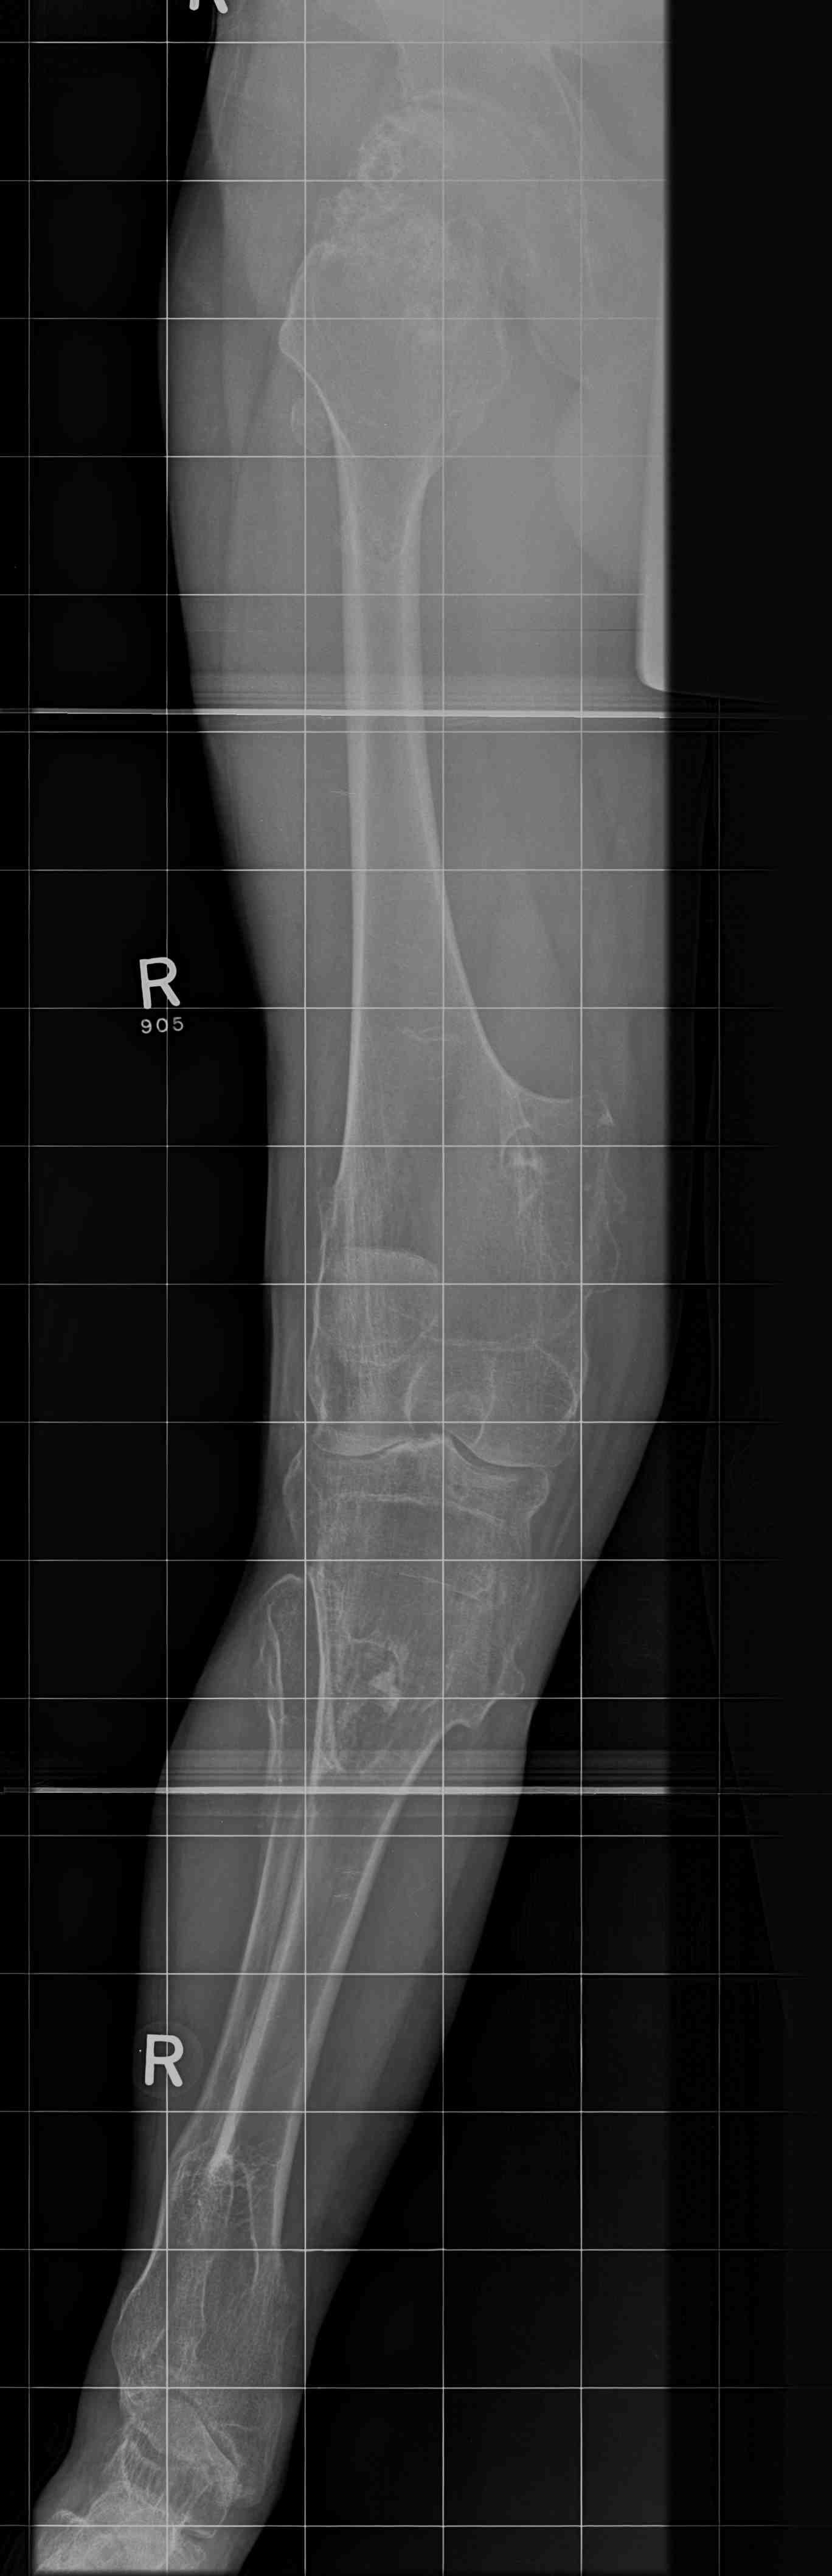

Lower limbs

- mildly short stature

- eg length discrepancies

- valgus knees / valgus ankle

- common peroneal compression

Knee - genu valgum

Genu Valgum OCMultiiple OCMultiple OC